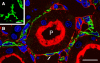

The renal interstitial compartment, situated between basement membranes of epithelia and vessels, contains two contiguous cellular networks. One network is formed by interstitial fibroblasts, the second one by dendritic cells. Both are in intimate contact with each other. Fibroblasts are interconnected by junctions and connected to basement membranes of vessels and tubules by focal adhesions. Fibroblasts constitute the "skeleton" of the kidney. In the renal cortex, fibroblasts produce erythropoietin and are distinguished from other interstitial cells by their prominent F-actin cytoskeleton, abundance of rough endoplasmic reticulum, and by ecto-5'-nucleotidase expression in their plasma membrane. The resident dendritic cells belong to the mononuclear phagocyte system and fulfil a sentinel function. They are characterized by their expression of MHC class II and CD11c. The central situation of fibroblasts suggests that signals from tubules, vessels, and inflammatory cells converge in fibroblasts and elicit an integrated response. Following tubular damage and inflammatory signals fibroblasts proliferate, change to the myofibroblast phenotype and increase their collagen production, potentially resulting in renal fibrosis. The acquisition of a profibrotic phenotype by fibroblasts in renal diseases is generally considered a main causal event in the progression of chronic renal failure. However, it might also be seen as a repair process.